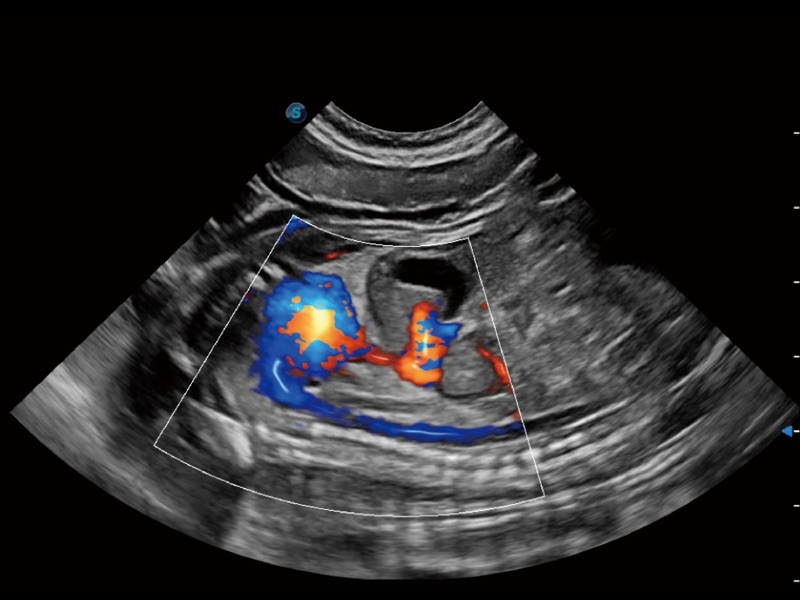

通过创新的 Matrix E自适应滤波器和超长时间域算法,极大提升超低速微细血流的检出能力,同时更精准地滤除软组织和噪声信号,为兽用医生提供以往无法通过常规血流获得的疾病诊断信息。